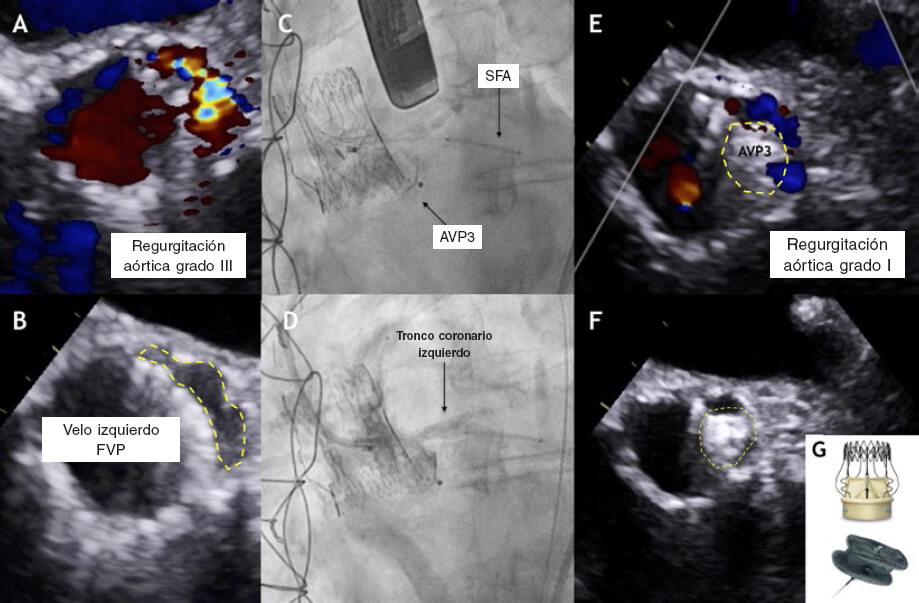

Mujer de 75 años intervenida de una sustitución valvular aórtica con el dispositivo sin sutura Perceval por degeneración de prótesis aórtica Mitroflow. La paciente ingresó 2 años después por insuficiencia cardiaca. Se realizó una ecocardiografía transesofágica (ETE) que reveló una fuga paravalvular (FPV) clase III en el velo coronario izquierdo, probablemente debida a una calcificación (figura 1A,B, vídeo 1 y vídeo 2 del material adicional). El equipo multidisciplinar optó por el cierre percutáneo de la FPV.

Figura 1.

La intervención se llevó a cabo utilizando un dispositivo Amplatzer Vascular Plug III de 10 x 5 mm (AVP3) (St. Jude Medical, Estados Unidos) (figura 1C-G, vídeo 3 y vídeo 4 del material adicional). Se colocó un stent farmacoactivo (SFA) no implantado en el tronco coronario izquierdo (TCI) para evitar posibles oclusiones. Después de la liberación, el TCI se mantuvo permeable y se procedió a recuperar el stent (figura 1D, vídeo 5 del material adicional). La ETE tras procedimiento confirmó el descenso significativo de la FPV (figura 1E,F). La tomografía computarizada multicorte (TCMC) que se realizó 6 meses después confirmó la relación anatómica entre el dispositivo AVP3, los velos de la prótesis Perceval y el TCI. Basándose en esta TCMD, se realizó un modelo en 3D que confirmó la ausencia de interferencias con los velos de la prótesis o el TCI. La ETE confirmó la presencia de TCI permeable y FPV leve (figura 2, vídeos 6-8 del material adicional).